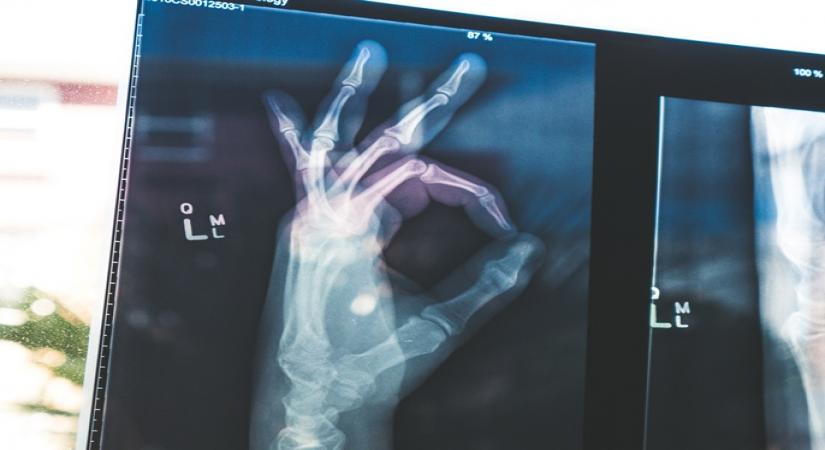

November 18, 2019 (IANSlife) Bones provide a structure to our body and protect our organs. Joints are complex structures of bones made functional by adjoining muscles. Joints allow movement and stability. Therefore, it is important to maintain them in good health says Dr Harshavardhan Hegde, Executive Director, Orthopaedics and Bone & Joint Surgery, Fortis Escorts Heart Institute.